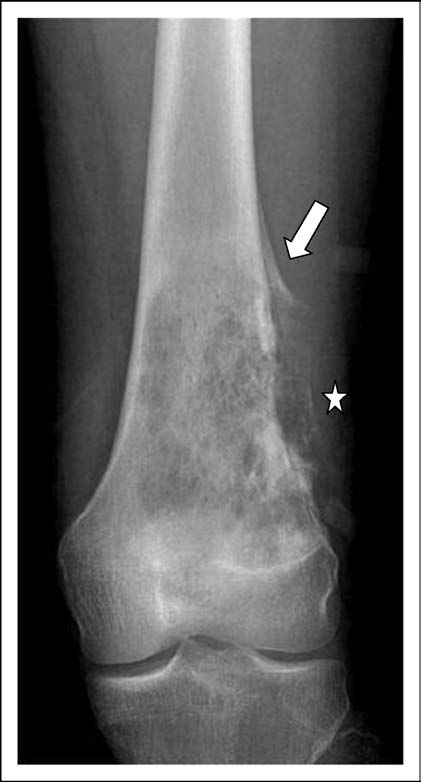

What does Codman triangle indicate when imaging a potential bone tumour?

Periosteal reaction which suggests a more slow-growing tumour